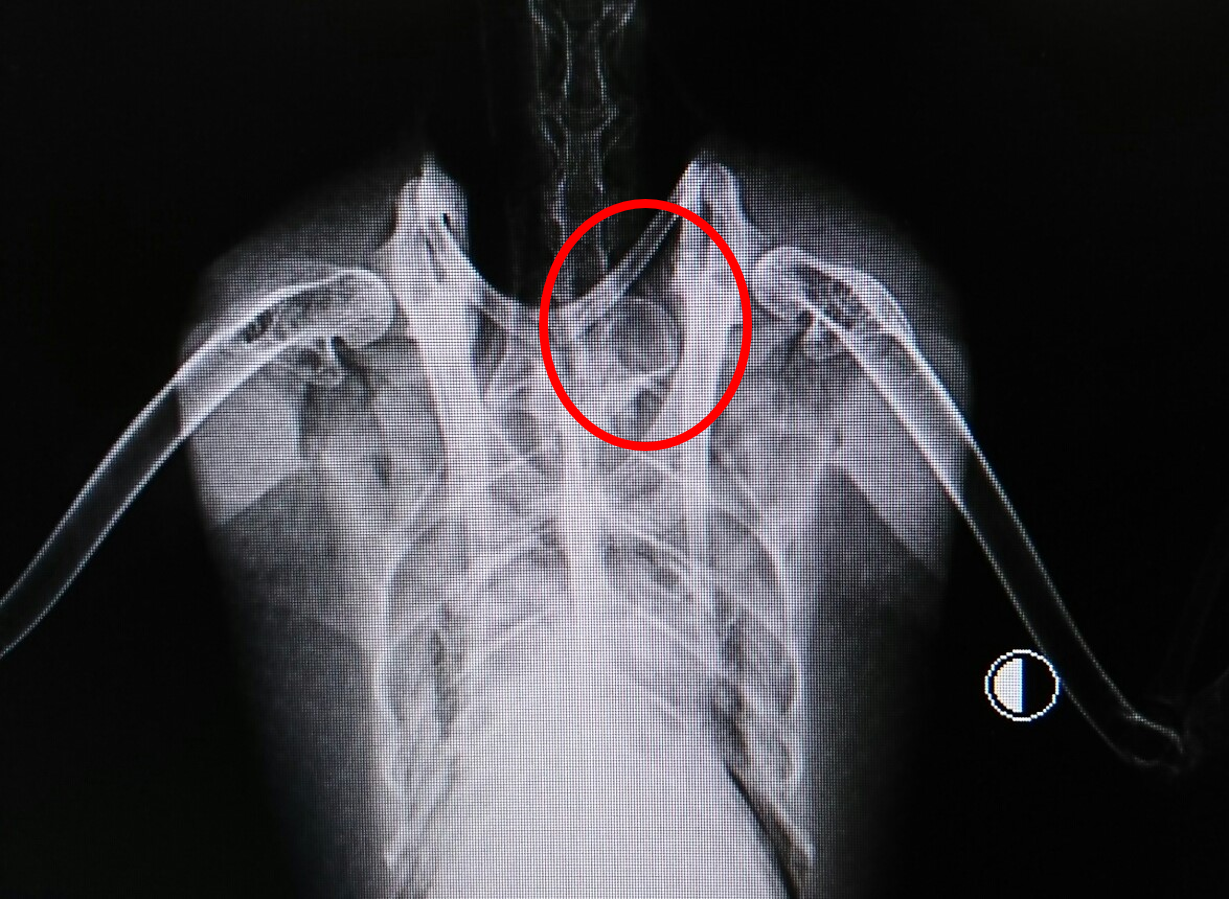

こっちがオス。

判別ポイントはここ↓

カルガモのオスは気管分岐部(鳴管)に膨らみがあります。それがレントゲンで写るのです。